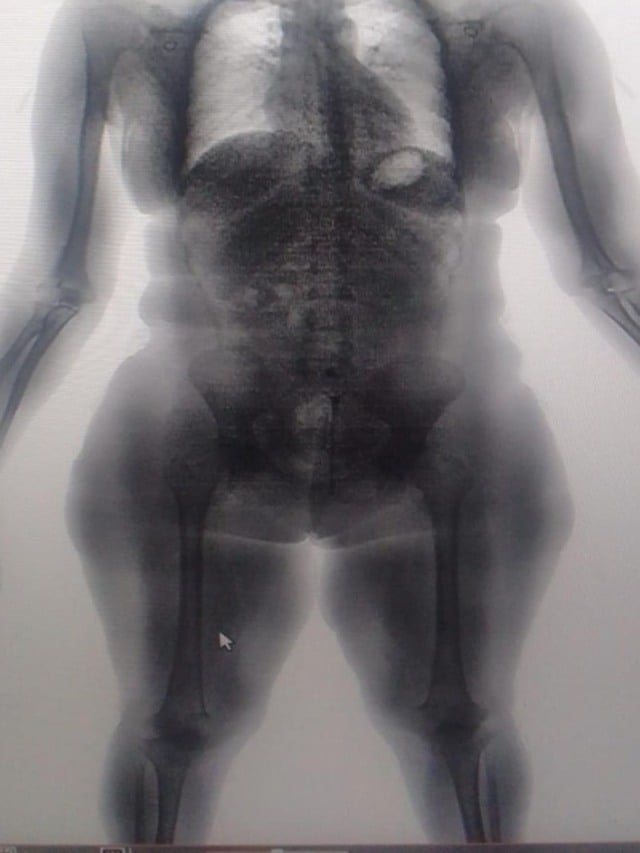

O caso aconteceu na quinta-feira (18), no Conjunto Penal de Lauro de Freitas, quando uma visitante foi flagrada pelas imagens do BodyScan, o scanner corporal usado nas revistas padrão das unidades prisionais do estado, com substâncias análogas à maconha e à cocaína em seu corpo. A mulher havia tentado burlar o mecanismo de revista introduzindo o material em suas partes íntimas.

No mesmo dia, mas no Conjunto Penal de Eunápolis, sete visitantes foram detidas ao tentar entrar com drogas escondidas em uma espécie de compartimento secreto nas sandálias. Uma delas ainda tentou esconder as substâncias em seu corpo, introduzindo-as nas partes íntimas. A tentativa de burlar o sistema também foi frustrada pelo preparo dos agentes e pelas imagens do BodyScan.